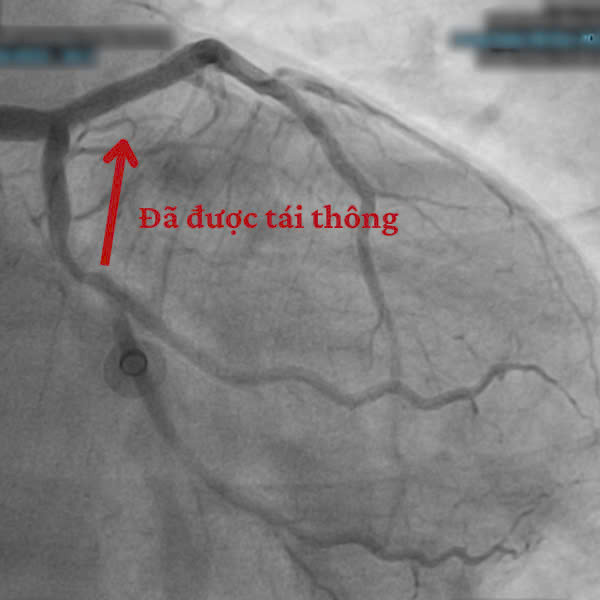

Ngay sau khi ổn định các chỉ số sinh tồn, người bệnh được đưa vào phòng Can thiệp Tim mạch. Qua hình ảnh chụp mạch vành, các bác sĩ phát hiện tắc hoàn toàn ngay sau lỗ động mạch liên thất trước (mạch máu chính nuôi tim).

![]() |

| Hình ảnh trên thiết bị can thiệp |

Bệnh nhân sau đó được chuyển đến khoa Hồi Sức Tích Cực (ICU) để tiếp tục theo dõi. Tình trạng bệnh nhân dần ổn định và phục hồi rất tốt, chỉ sau 5 ngày đã được xuất viện về với gia đình.